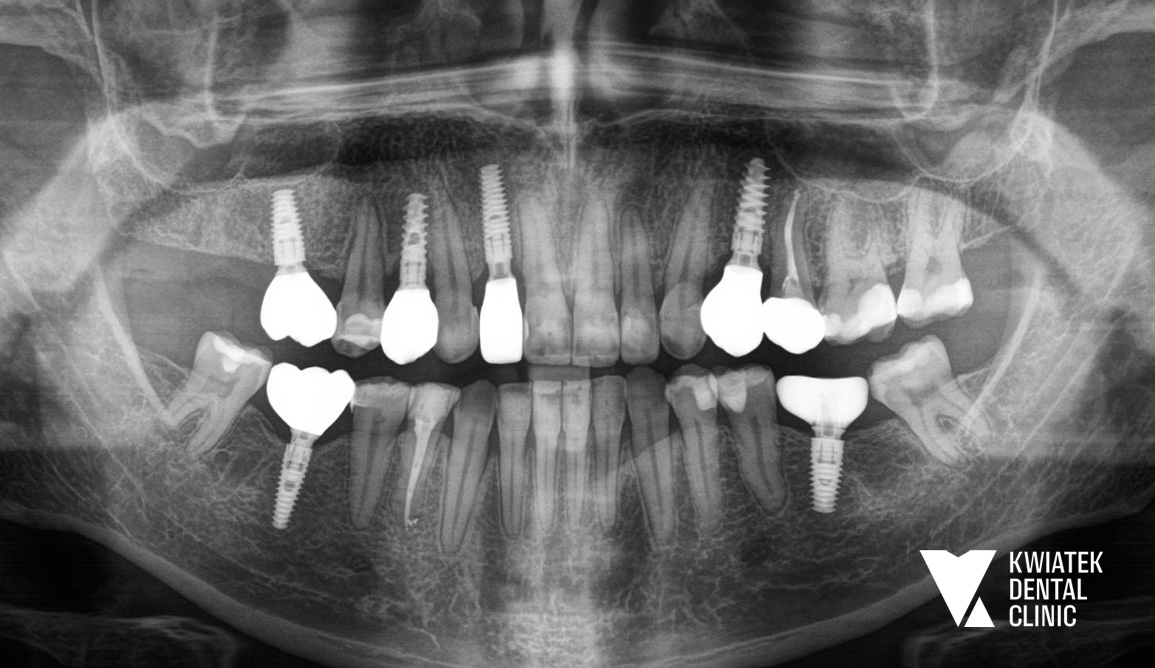

Diagnostyka była prowadzona etapowo z wykorzystaniem tomografii CBCT, skanów wewnątrzustnych oraz dokumentacji radiologicznej i fotograficznej, co pozwoliło na precyzyjne planowanie leczenia w perspektywie długoterminowej.

Rozpoczęto od zabiegów chirurgicznych i usunięcia zębów niekwalifikujących się do leczenia. Następnie wdrożono zaawansowane procedury implantologiczne, w tym natychmiastowe implantacje oraz zabiegi augmentacji kości z użyciem biomateriałów.

W przypadku zęba 24 konieczne było ponowne podejście implantologiczne po braku integracji, które zakończyło się powodzeniem. W odcinku przednim zastosowano nowoczesne techniki implantacji natychmiastowej, zapewniające zachowanie estetyki już na etapie leczenia.